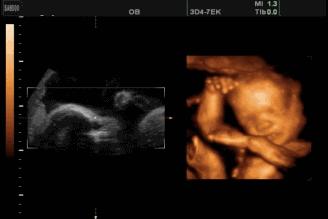

我们都知道四维检查就是大排畸检查,三维检查也能做大排畸,但是四维多了一个时间维度,可以看到胎儿的动态图像,能观察到胎儿的运动神经是否正常,所以四维还是更有优势一些。

- 头面部:眼睛、鼻子、嘴巴、大脑,能排除脑积水、唇裂等问题。

- 内脏器官:心脏、脾脏、肾脏、肠管、胃、肝脏等全部内脏器官。

- 四肢:双手、双脚。

脊柱排列是否整齐连续,可以排除脊柱裂。